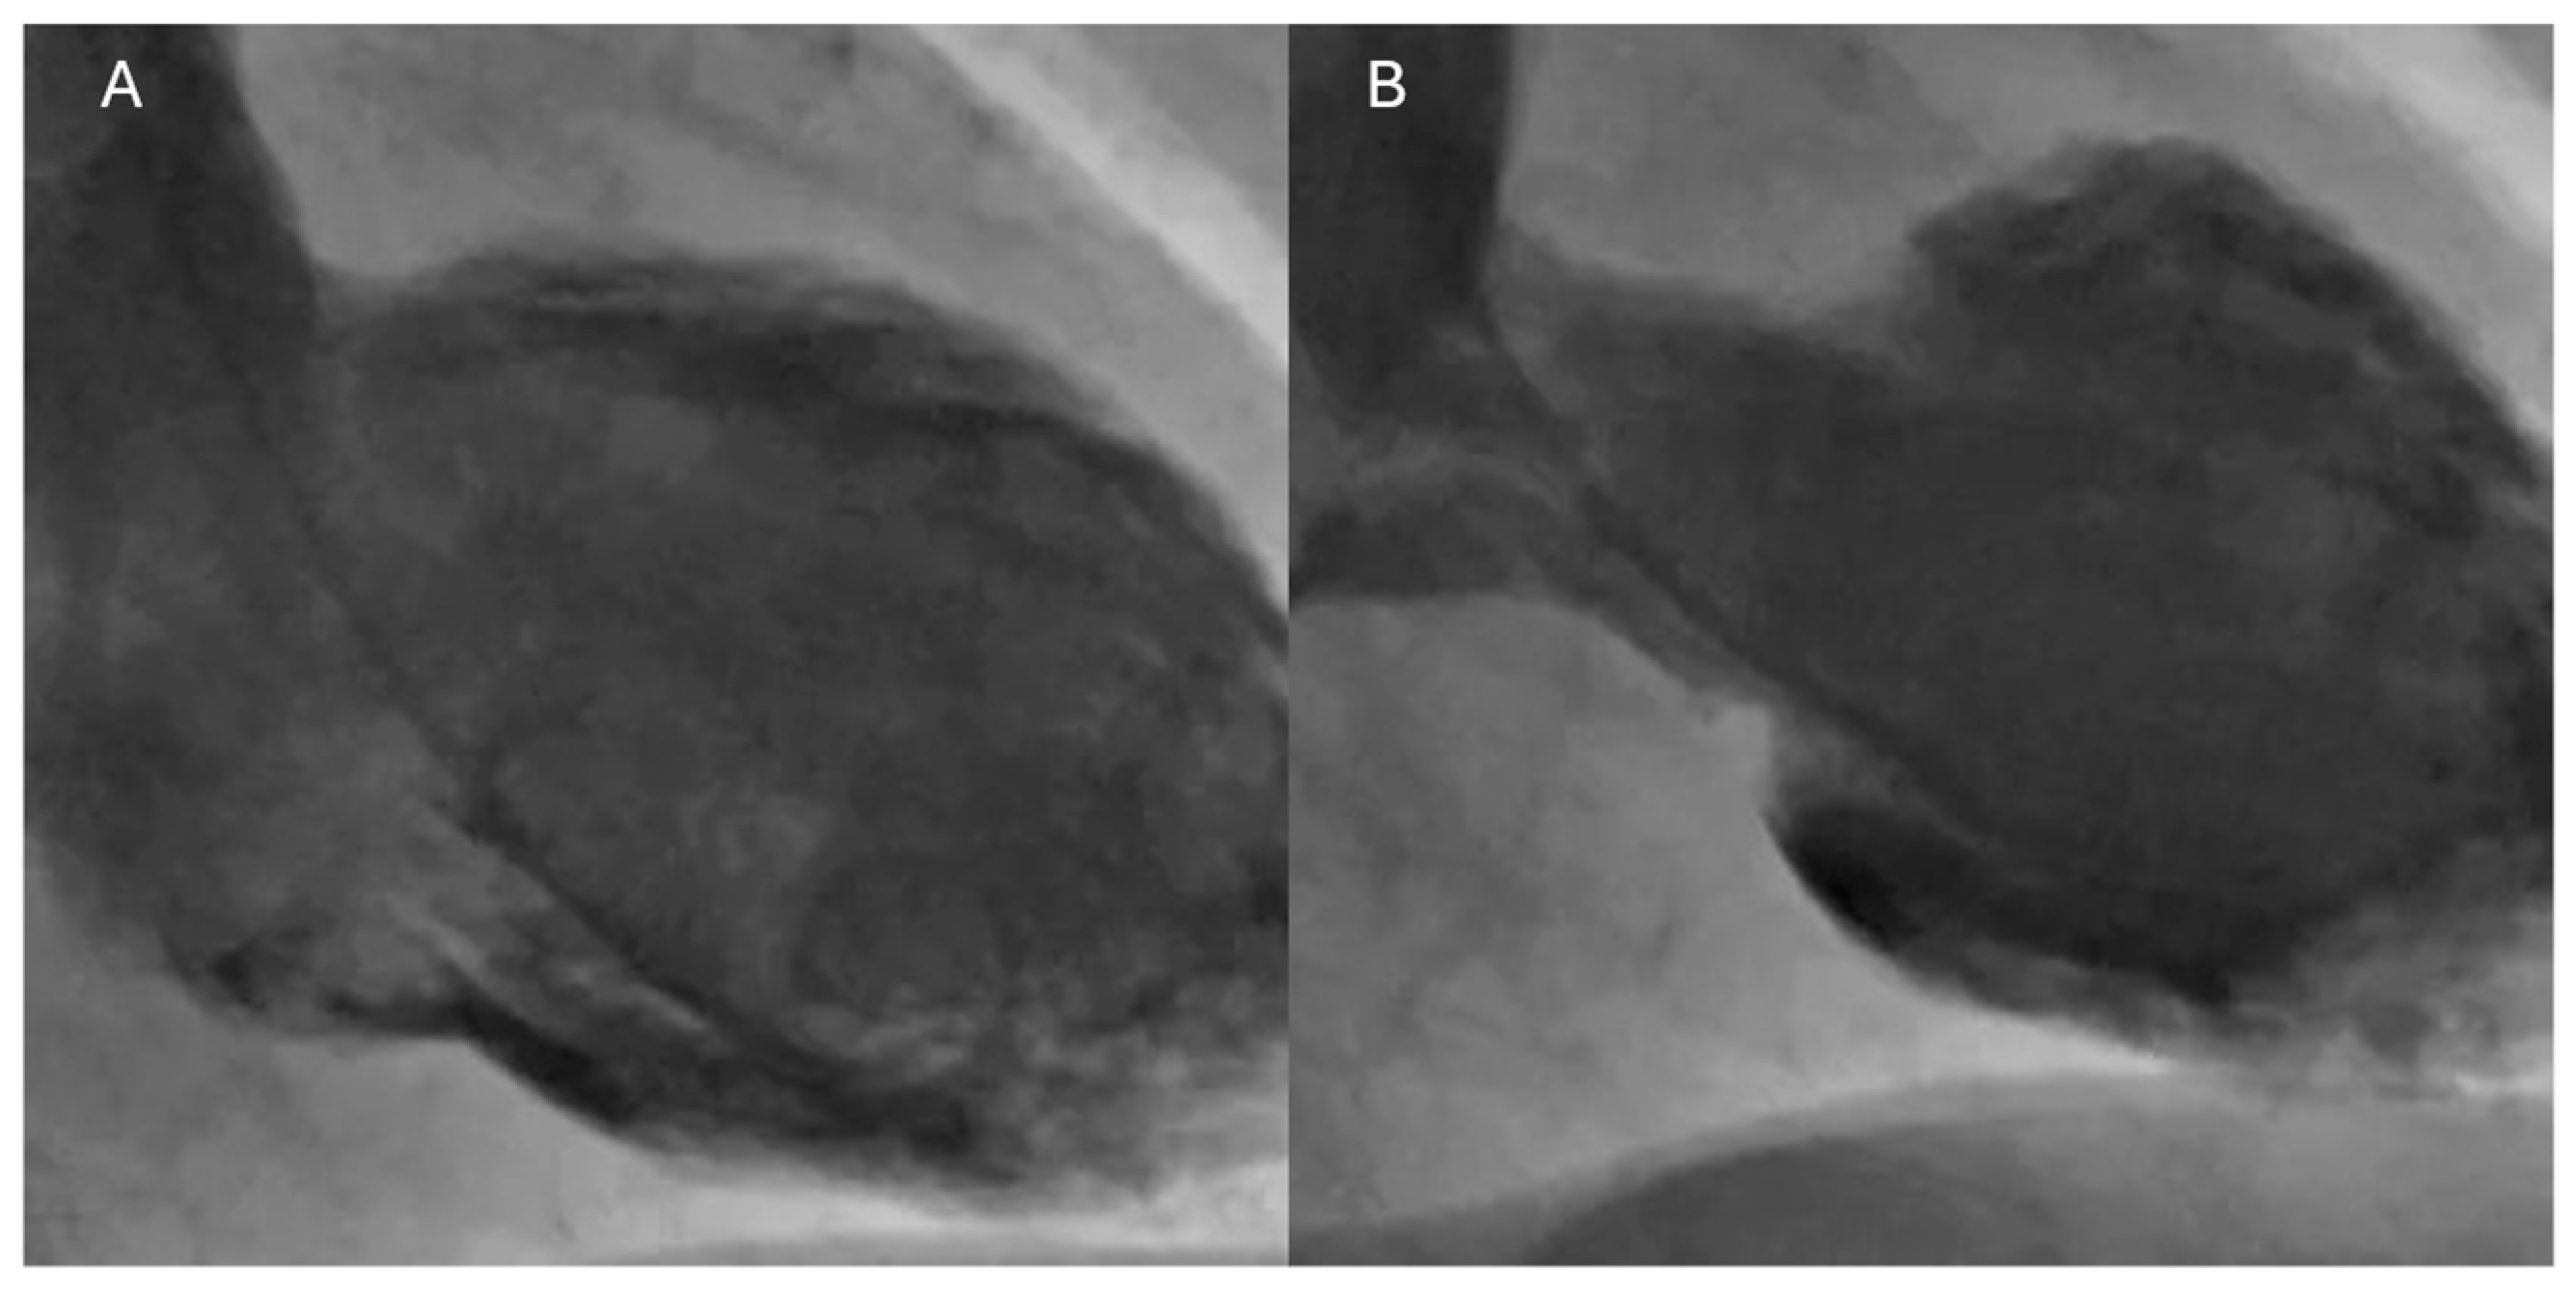

6.5. Coronary Angiography and Ventriculography